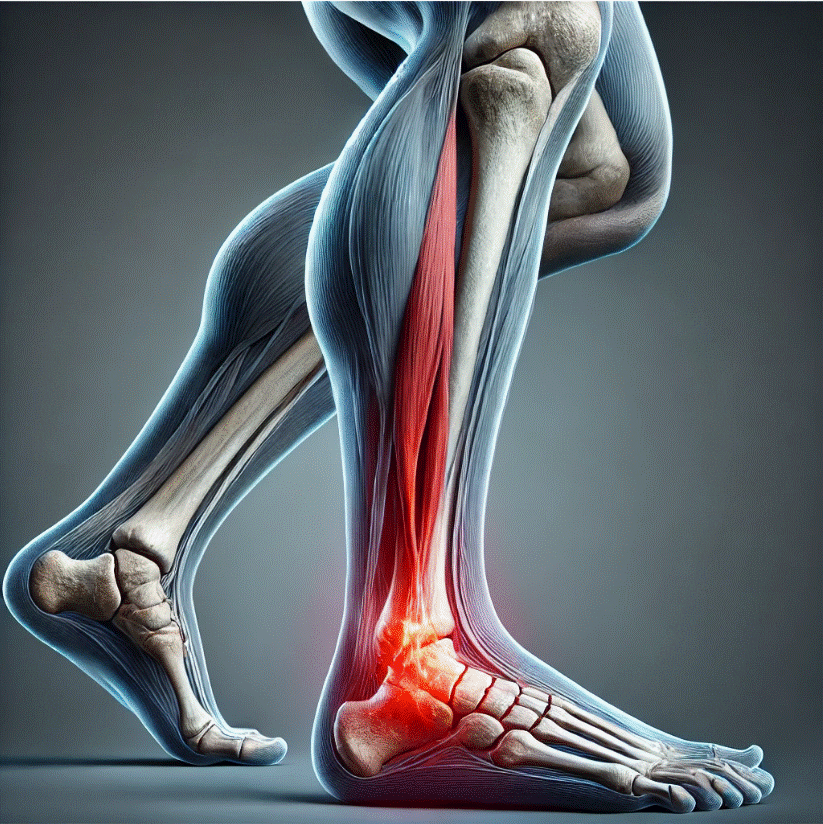

Periostitis tibial y tendón de Aquiles en corredores: importancia de la biomecánica

La periostitis tibial y las lesiones en el tendón de Aquiles son dos de los problemas más frecuentes en corredores de todos los niveles. Factores biomecánicos, como una técnica de carrera deficiente o desequilibrios musculares, pueden predisponer a sufrir estas patologías. La correcta evaluación y tratamiento desde la fisioterapia especializada permite no solo recuperar la […]